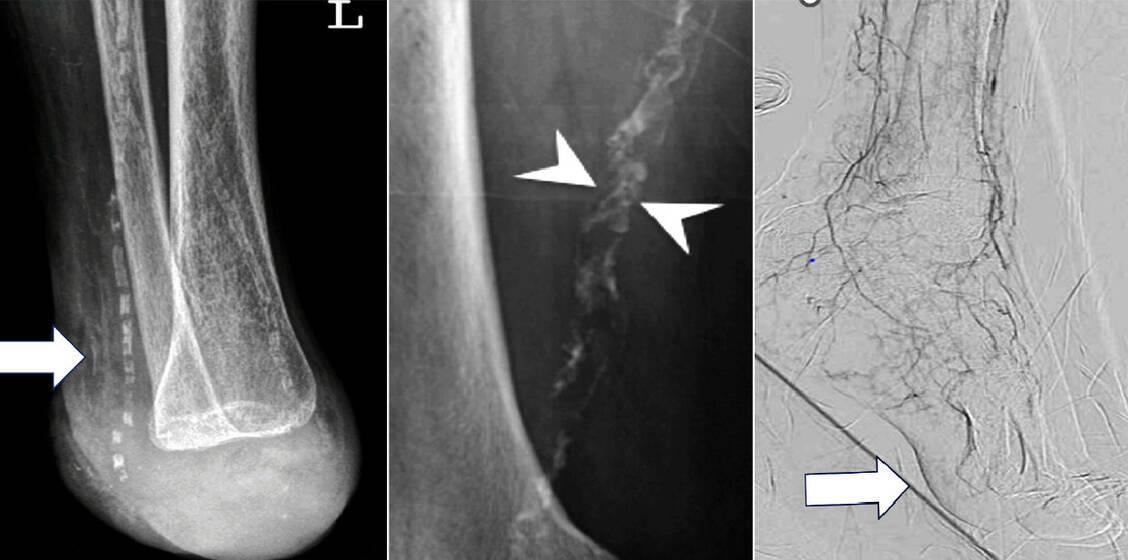

Die Kalzifikation kommt in drei Varianten vor. Bei der Mediasklerose handelt es sich um eine zirkuläre Verkalkung in der Muskelschicht der Gefäßwand (9). Im Röntgenbild sieht man einen »Tramline-Aspekt« (Abbildung 2). Die Mediasklerose selbst verengt das Lumen der betroffenen Gefäße nicht relevant, erhöht aber deren Steifigkeit. Langfristig kann sie einen Lumenverlust vor allem in den dünneren Leitungsarterien des Unterschenkels verstärken (10).

Die Mediasklerose und die verstärkten Plaqueverkalkungen erschweren interventionelle und operative Revaskularisationen (Wiedereröffnung von Gefäßen). Dagegen schränkt die SAD die Perfusion des Vorfußes und der Zehen kontinuierlich bis hin zu einem nicht mehr durchbluteten »Desert-Foot« ein (Abbildung 2). Entsprechend schlecht ist die Prognose hinsichtlich eines -Zehen- und Vorfußerhalts (8–11).